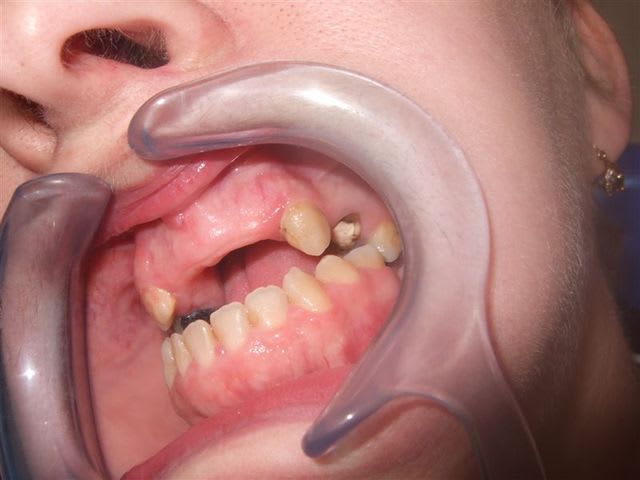

Cheese

mouais, dommage de virer les 9 dents antérieures mandibulaires (inc + PM) quand même. Elle semble avoir un paro en béton avec des dents encore bien implantées.

A première vue et de façon subjective, j'aurais tendance à virer toutes les dents maxillaires + régularisation osseuse des secteurs post. En bas, je virerais les molaires.

Puis complet haut et stellite bas tout simplement. Au mieux, on peut espérer mettre les dents en bout à bout dans le secteur antérieur.

Ce qui me chagrine le plus est comment gérer la DV très faible dans la zone postérieure. La hauteur des dents prothétiques risque d'être assez réduite à ce niveau s'il l'on ne veut pas surélever exagérement la DV.

En faisant une régularisation de la crête + avec la résorption physiologique post-extractionnelle, on gagnera quelques millimétres salvateurs mais pas suffisamment.

Il faudra alors augmenter la DV. Dans ce cas, je pense que je le ferais avec beaucoup de prudence et très modérement (2-3 mm en ant). Si on augmente plus, on risque de rompre un équilibre fragile et difficile à maitriser au niveau des ATM.

Augmenter de façon importante une DV ne me pose pas trop de soucis en général mais dans ce cas précis, je serais très prudent...